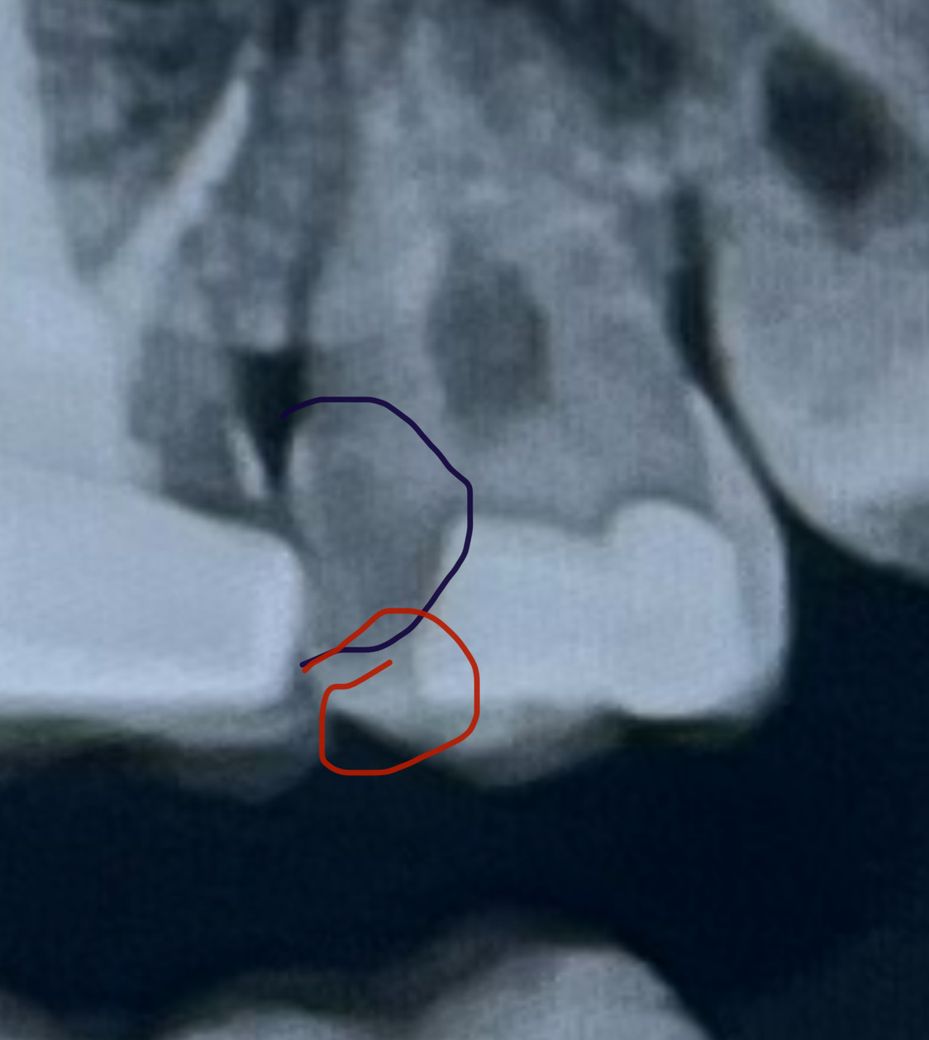

빨간 부분이 제가 체감하고 있는 구멍쪽이고 검은 부분은 예전에 치과 두곳에서 신경치료를 권유 하셨었어요

• 1번 째 사진

엑스레이 상으로만 보면 충치가 진행이 됫거나 치아가 깨진상태 같습니다 .저정도 상태라면 신경치료를 해야될것같습니다.

사진으로 봤을 경우에는 인접면의 충치가 넓어진것으로 보입니다. 충치를 제거했을 경우 신경이 노출될 가능성이 높으며 인접면이기 때문에 신경치료후에 보철치료를 하는것이 좋을것으로 생각됩니다.

2. 구멍과 함께 아말감 하방으로 이차우식이 있어보이네요